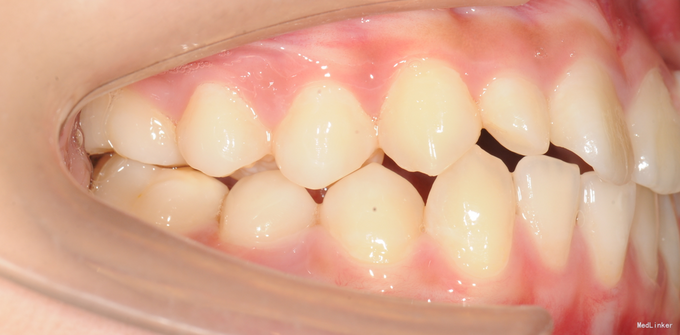

13岁女孩,主诉门牙不美观,要求改善

直面型,左上乳2仍存,口内未见恒2,下前牙口内只有3颗。上下牙齿轻度拥挤不齐。全景示下前牙先天缺失一颗,左上恒2垂直埋伏阻生。